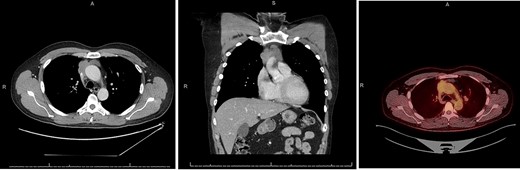

A 55-year-old male initially presented to his primary care provider with diplopia and eyelid droop. He was diagnosed with MG via confirmation of positive acetylcholine receptor blocking antibodies. CT chest revealed a complex, multilobulated, 6 cm anterior mediastinal mass compressing the SVC and possibly involving the central aspect of the left innominate vein(Fig. 1). A core needle biopsy was obtained, and pathology was consistent with type B2 thymoma, with no evidence of carcinoma. A positron emission tomography (PET) scan was also obtained, which revealed a maximum standard uptake value (SUVmax) of 3.0. Treatment was discussed across multiple disciplines at multiple institutions, with differing opinions regarding neoadjuvant chemotherapy, definitive chemoradiation due to unresectability, versus upfront surgical resection. Our facility, a major regional thoracic oncology center, was consulted and recommended upfront surgical resection followed by likely adjuvant radiation.

CT chest axial (left), coronal (middle) and PET (right) of invasive thymoma.